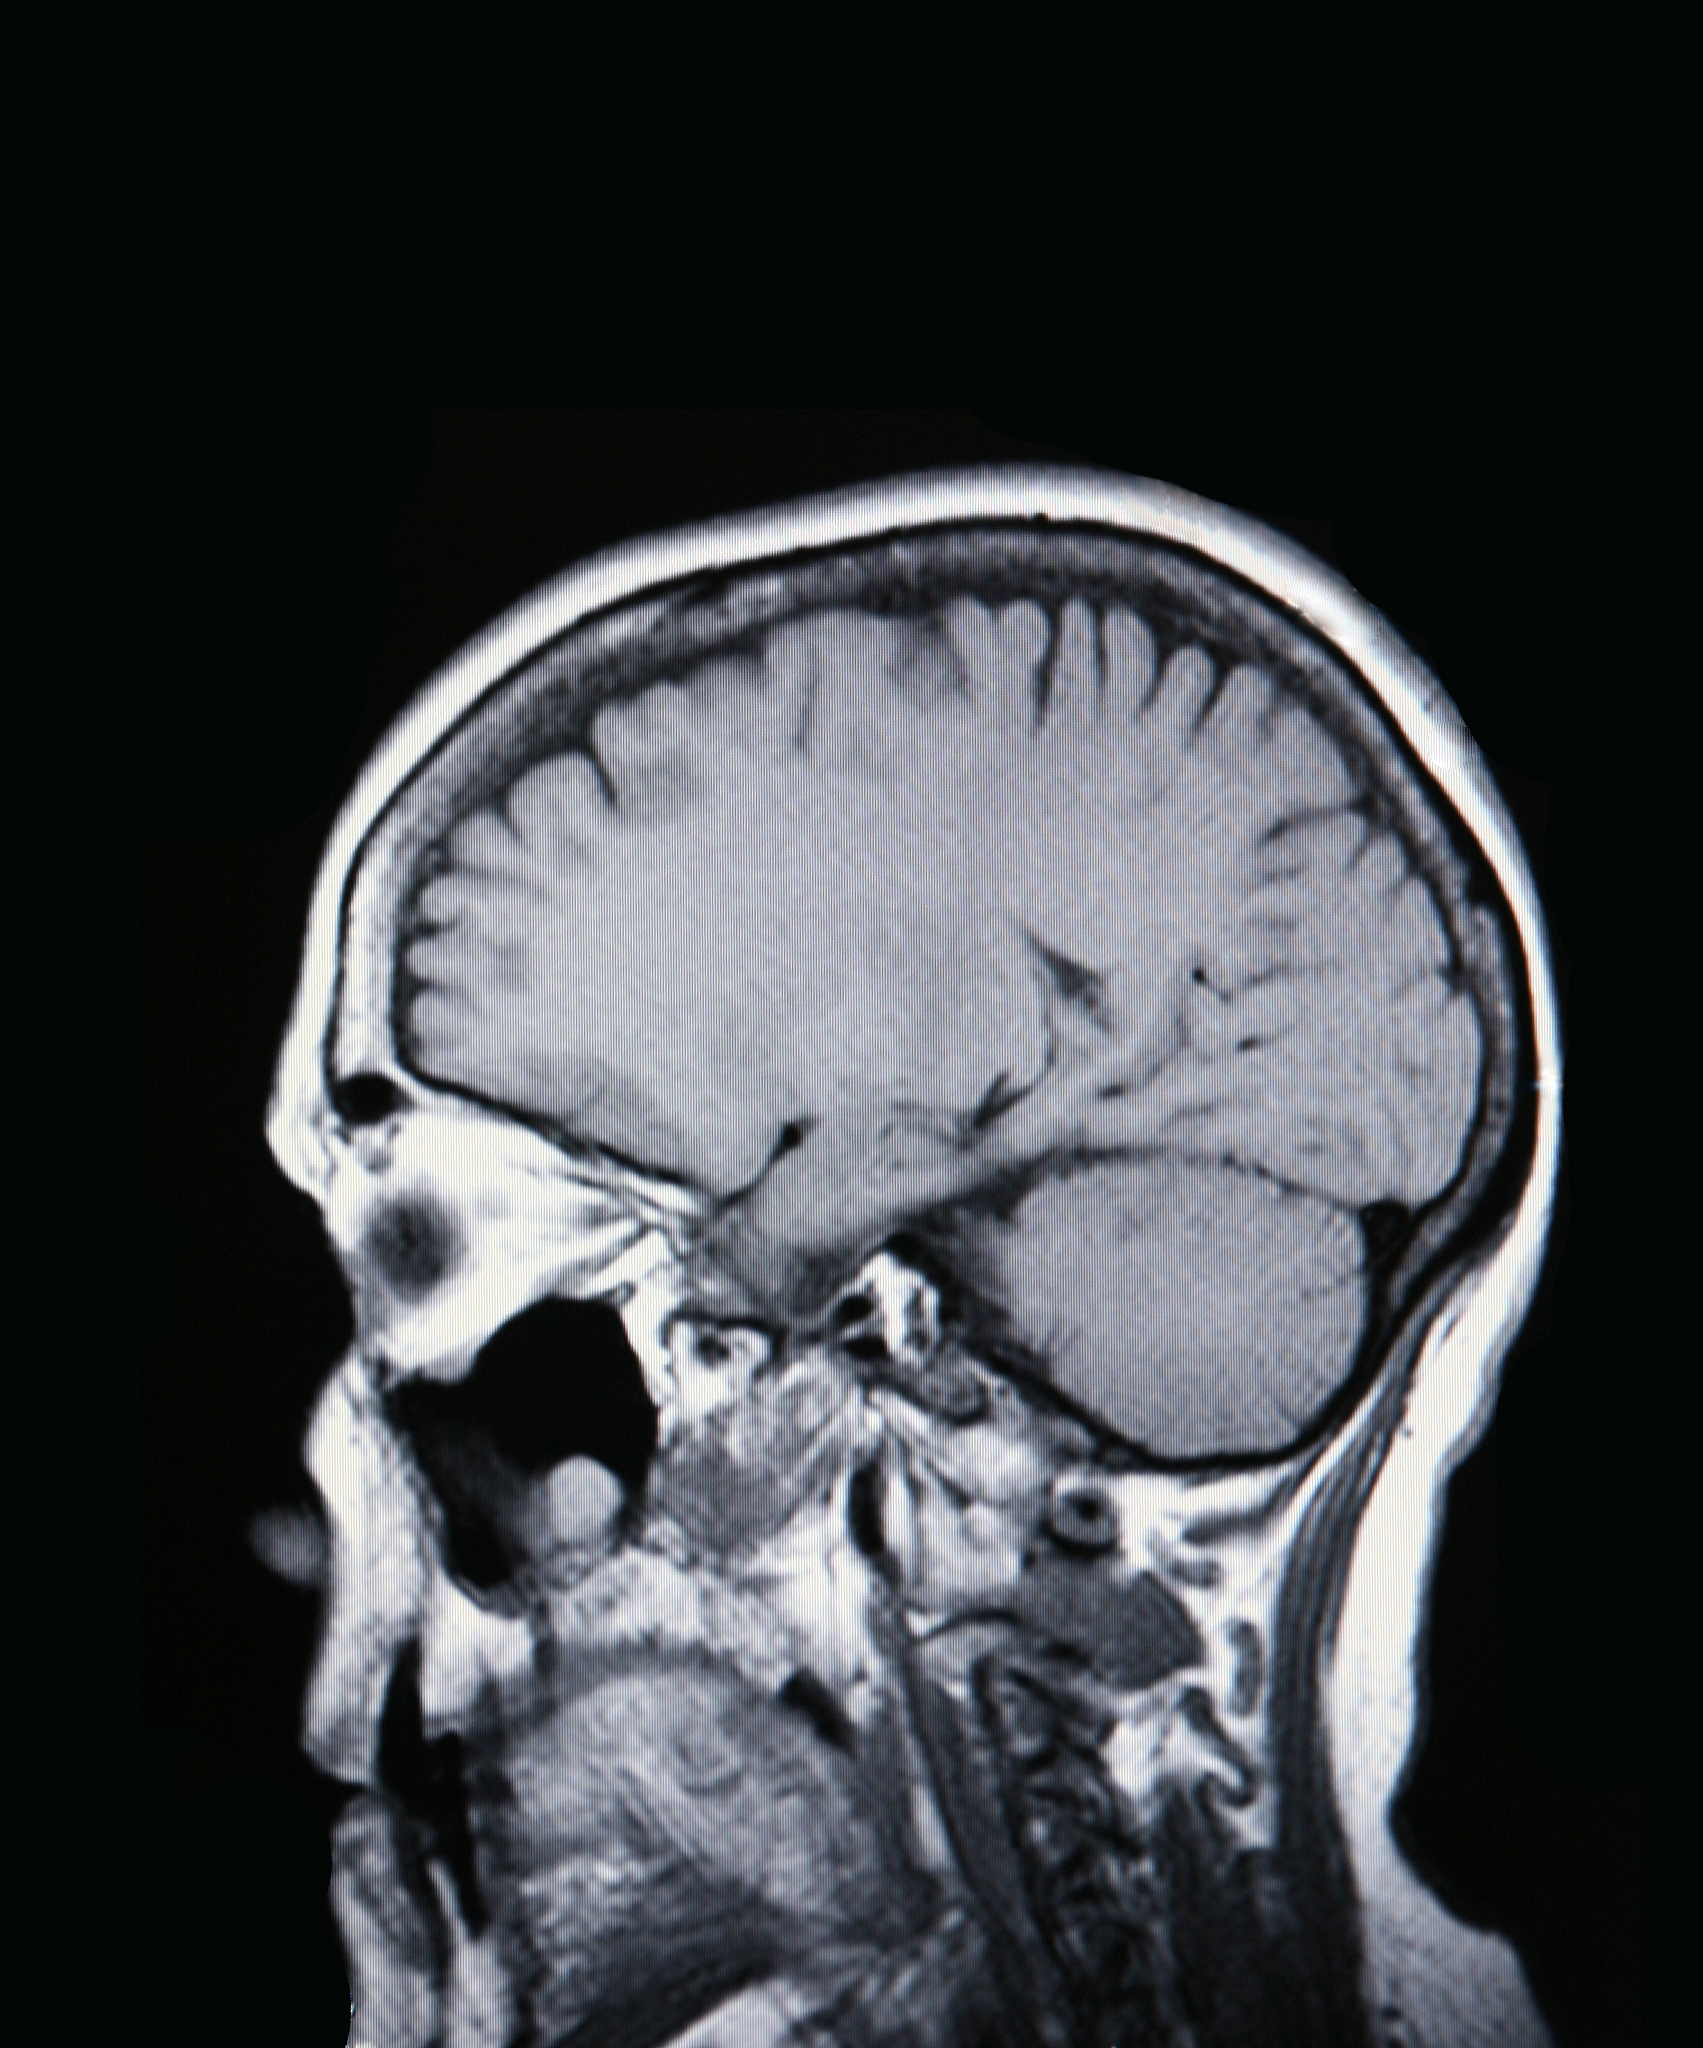

小脑扁桃体下疝伴相应颈髓受压变形问题严重吗

这个问题需要更多的背景信息和具体的医学诊断才能给出准确的答案。小脑扁桃体下疝是指小脑扁桃体向颅腔内突出,可能会对颅内结构造成一定的影响。相应颈髓受压变形也可能会对神经系统造成影响。但是具体的严重程度需要根据患者的具体情况来评估。建议患者咨询医生,进行详细的检查和诊断。